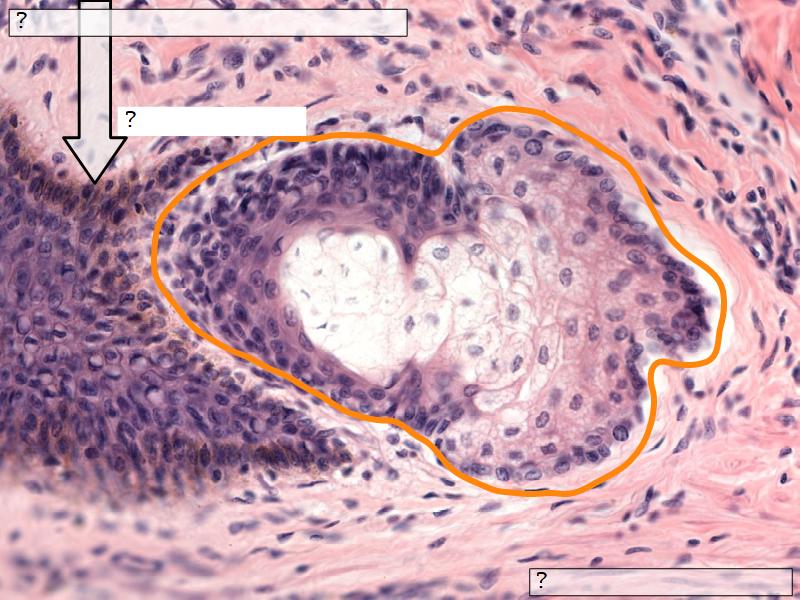

What are the main morphological features of the nipple?

Morphology

Skin

- Keratinized stratified squamous epithelium

- Sebaceous glands